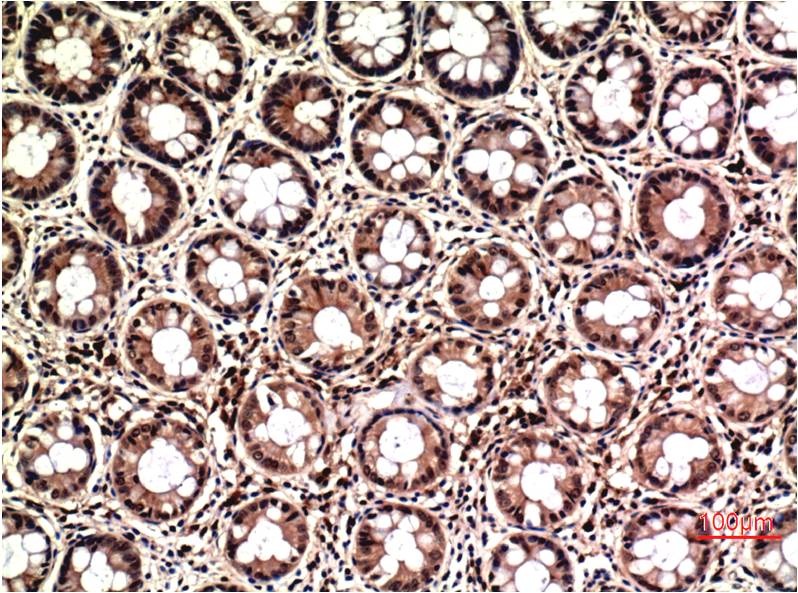

Immunohistochemistry analysis of paraffin-embedded Human Colon Carcinoma Tissue using ERK1/2 antibody. High-pressure and temperature Sodium Citrate pH 6.0 was used for antigen retrieval. |